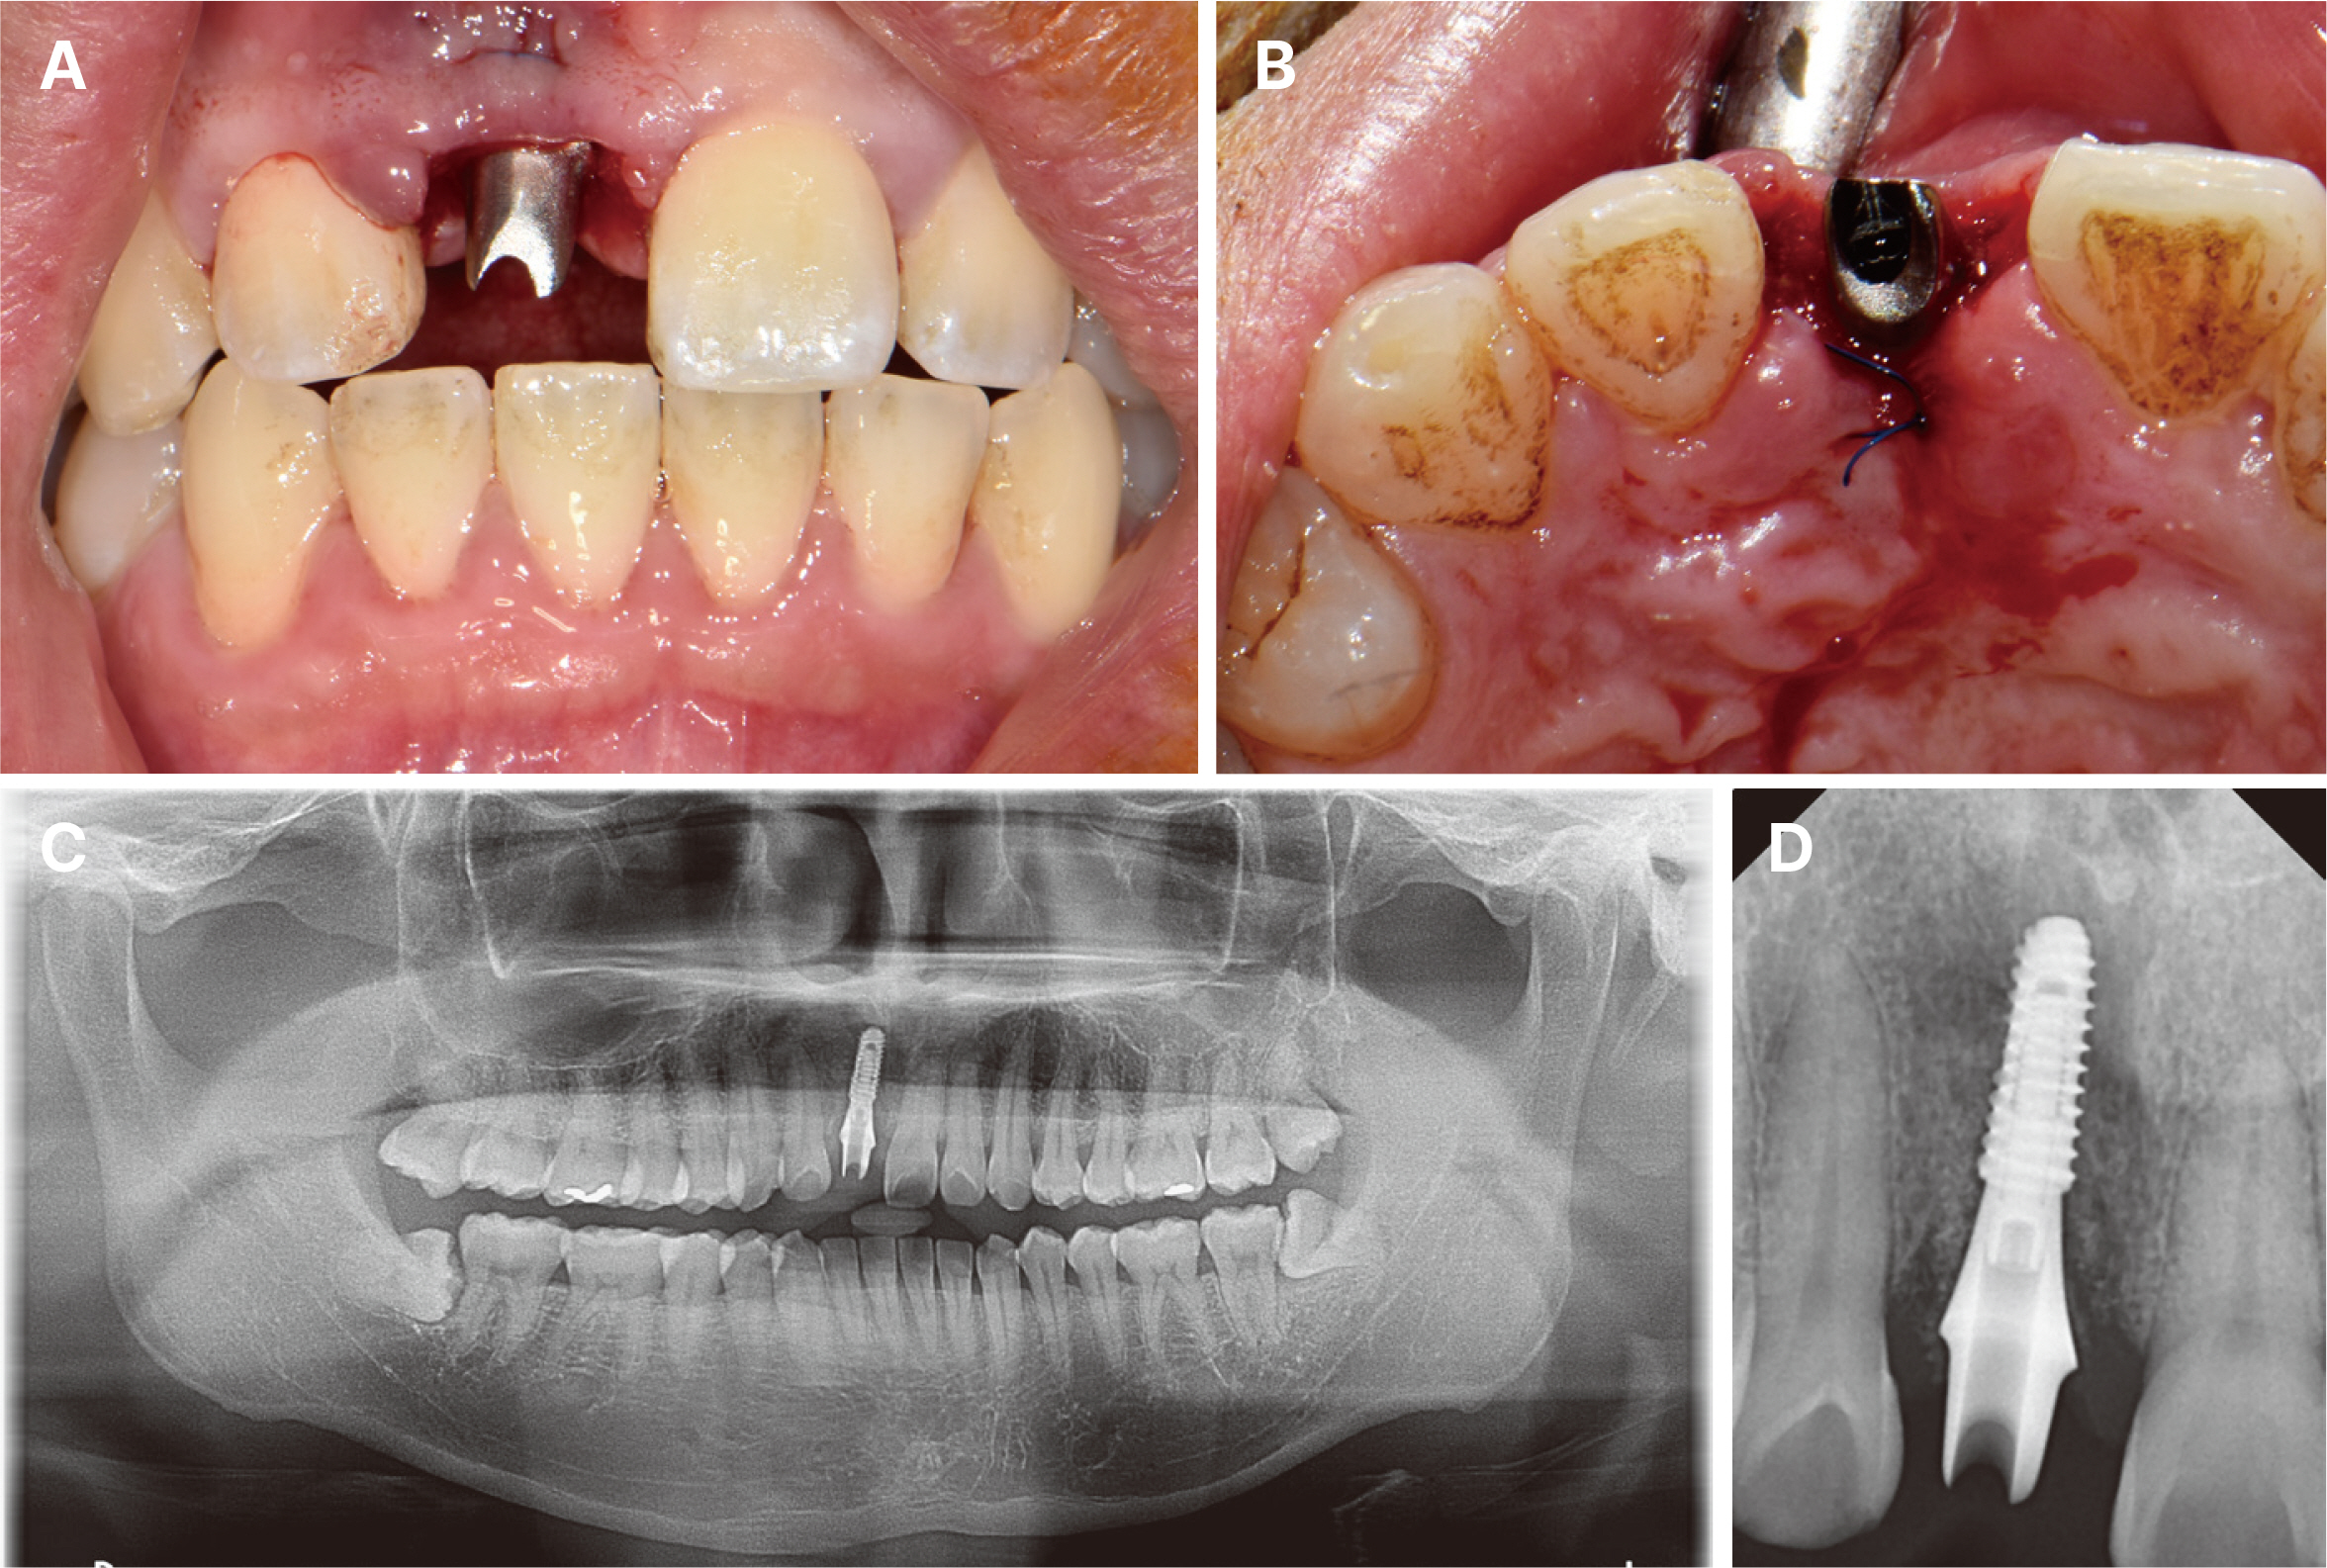

- Immediate implant placement and immediate loading in the anterior maxilla is an effective approach to rapidly address aesthetic demands. To achieve successful outcomes, bone quality, soft tissue condition, and accurate implant positioning are essential factors. For optimal results, procedures such as bone augmentation, precise implant placement, and, when necessary, soft tissue grafting should be considered. Furthermore, provisional restoration play a crucial role in achieving the desired appearance of prosthetic restorations and improving the aesthetics of the soft tissue. By performing soft tissue molding through provisional restoration, an ideal emergence profile can be established, which can be subsequently transferred to the final prosthesis, leading to a functional and aesthetically pleasing restoration. This approach aims to optimize the aesthetic outcomes in the anterior region while preserving the natural contours of the peri-implant soft tissue. In this case, a patient requiring extraction of maxillary anterior tooth underwent immediate implantation and alveolar bone grafting using a guide fabricated in advance from CT data. The patient received a provisional restoration on the same day. Subsequent steps included transitioning from the provisional prosthesis to the definitive prosthesis, ultimately achieving an aesthetically pleasing and functional implant restoration. We report this case to highlight the successful approach to maxillary anterior implant rehabilitation.